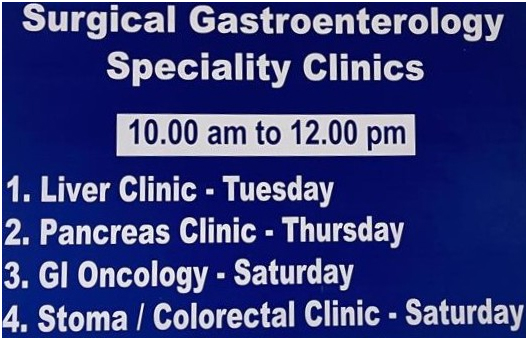

Special Clinics

Venue: OP 146, 2nd Floor, PMSSY Block, GMKMCH, Salem.

| S. No. | Name Of The Clinic | Days | Timings |

|---|---|---|---|

| 1 | LIVER CLINIC | Tuesdays | 10:00 AM to 12:00 PM |

| 2 | PANCREAS CLINIC | Thursdays | 10:00 AM to 12:00 PM |

| 3 | GI ONCOLOGY CLINIC | Saturdays | 10:00 AM to 12:00 PM |

| 4 | STOMA / COLORECTAL CLINIC | Saturdays | 10:00 AM to 12:00 PM |